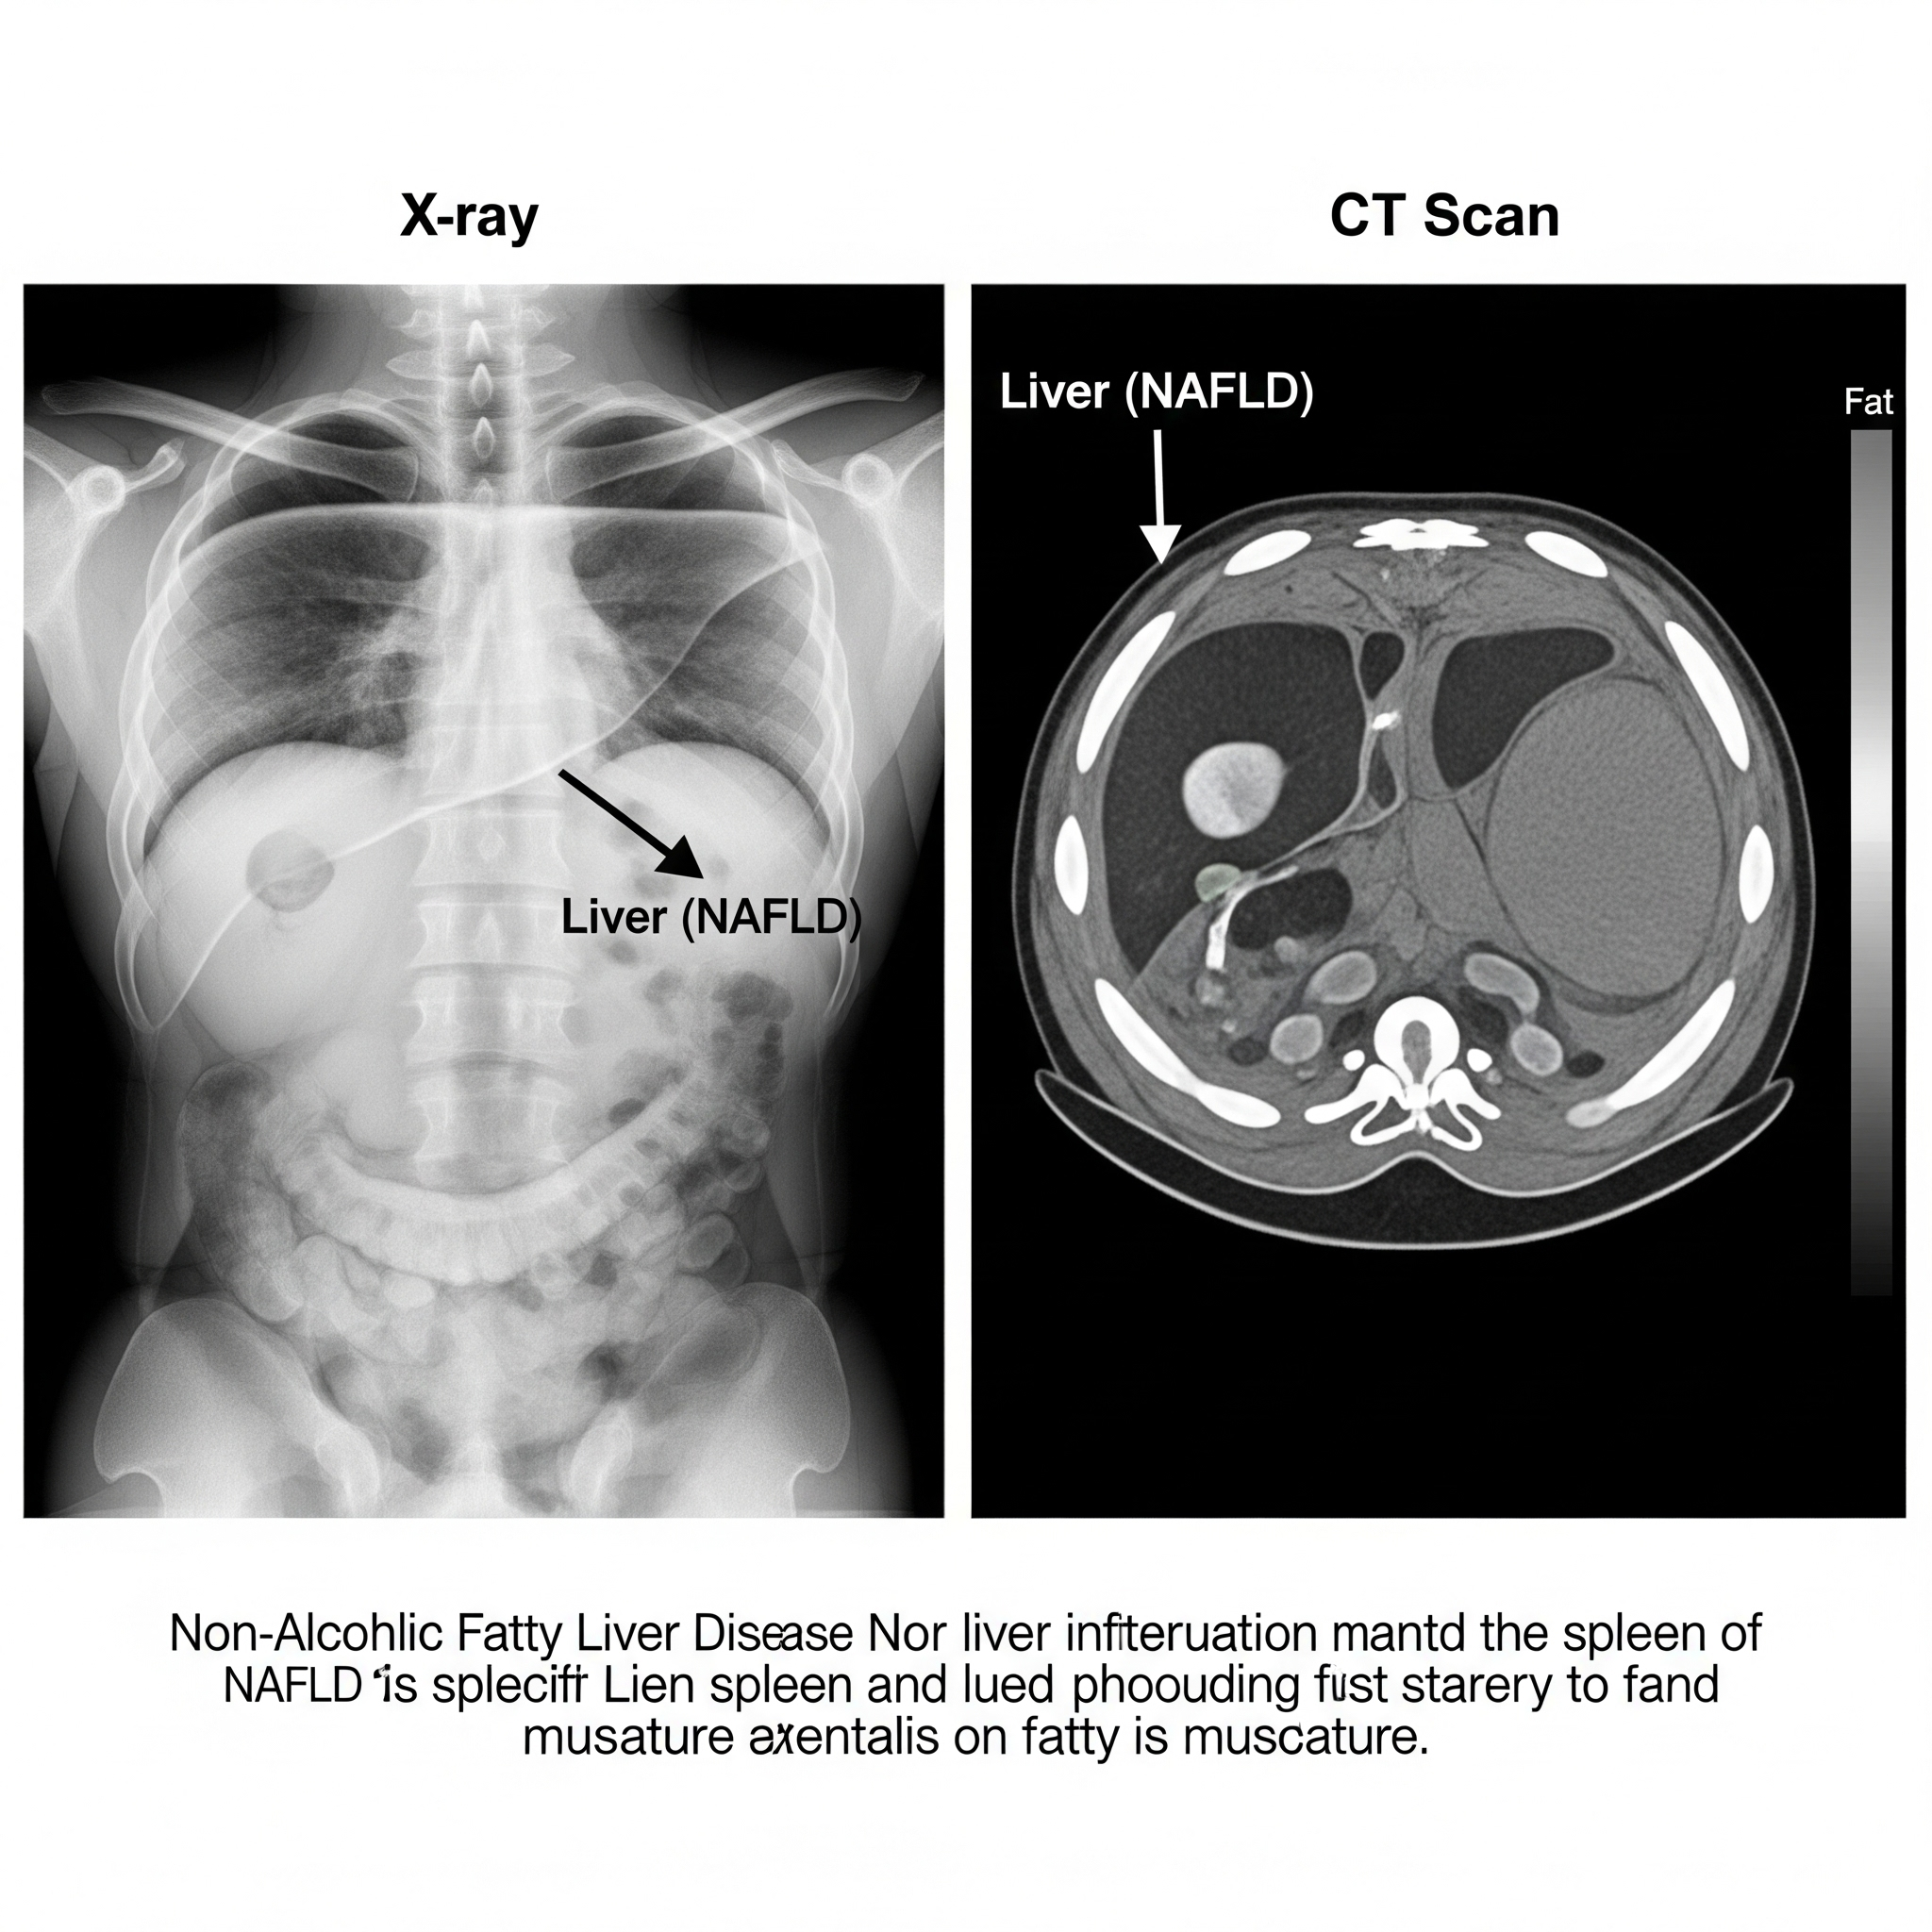

Background: Non-alcoholic fatty liver disease (NAFLD) is now recognized as the most common chronic liver disease globally, affecting nearly one in four adults. Despite its prevalence, NAFLD is often underdiagnosed in primary care, where opportunities for early intervention are frequently missed. Reliable, accessible tools for early detection are urgently needed to prevent progression to cirrhosis and hepatocellular carcinoma.

Conclusion: Integrating simple biomarker screening with liver ultrasound significantly improves early detection of NAFLD in primary care. This combined approach is feasible, cost-effective, and could be incorporated into routine health checks to prevent advanced liver disease.